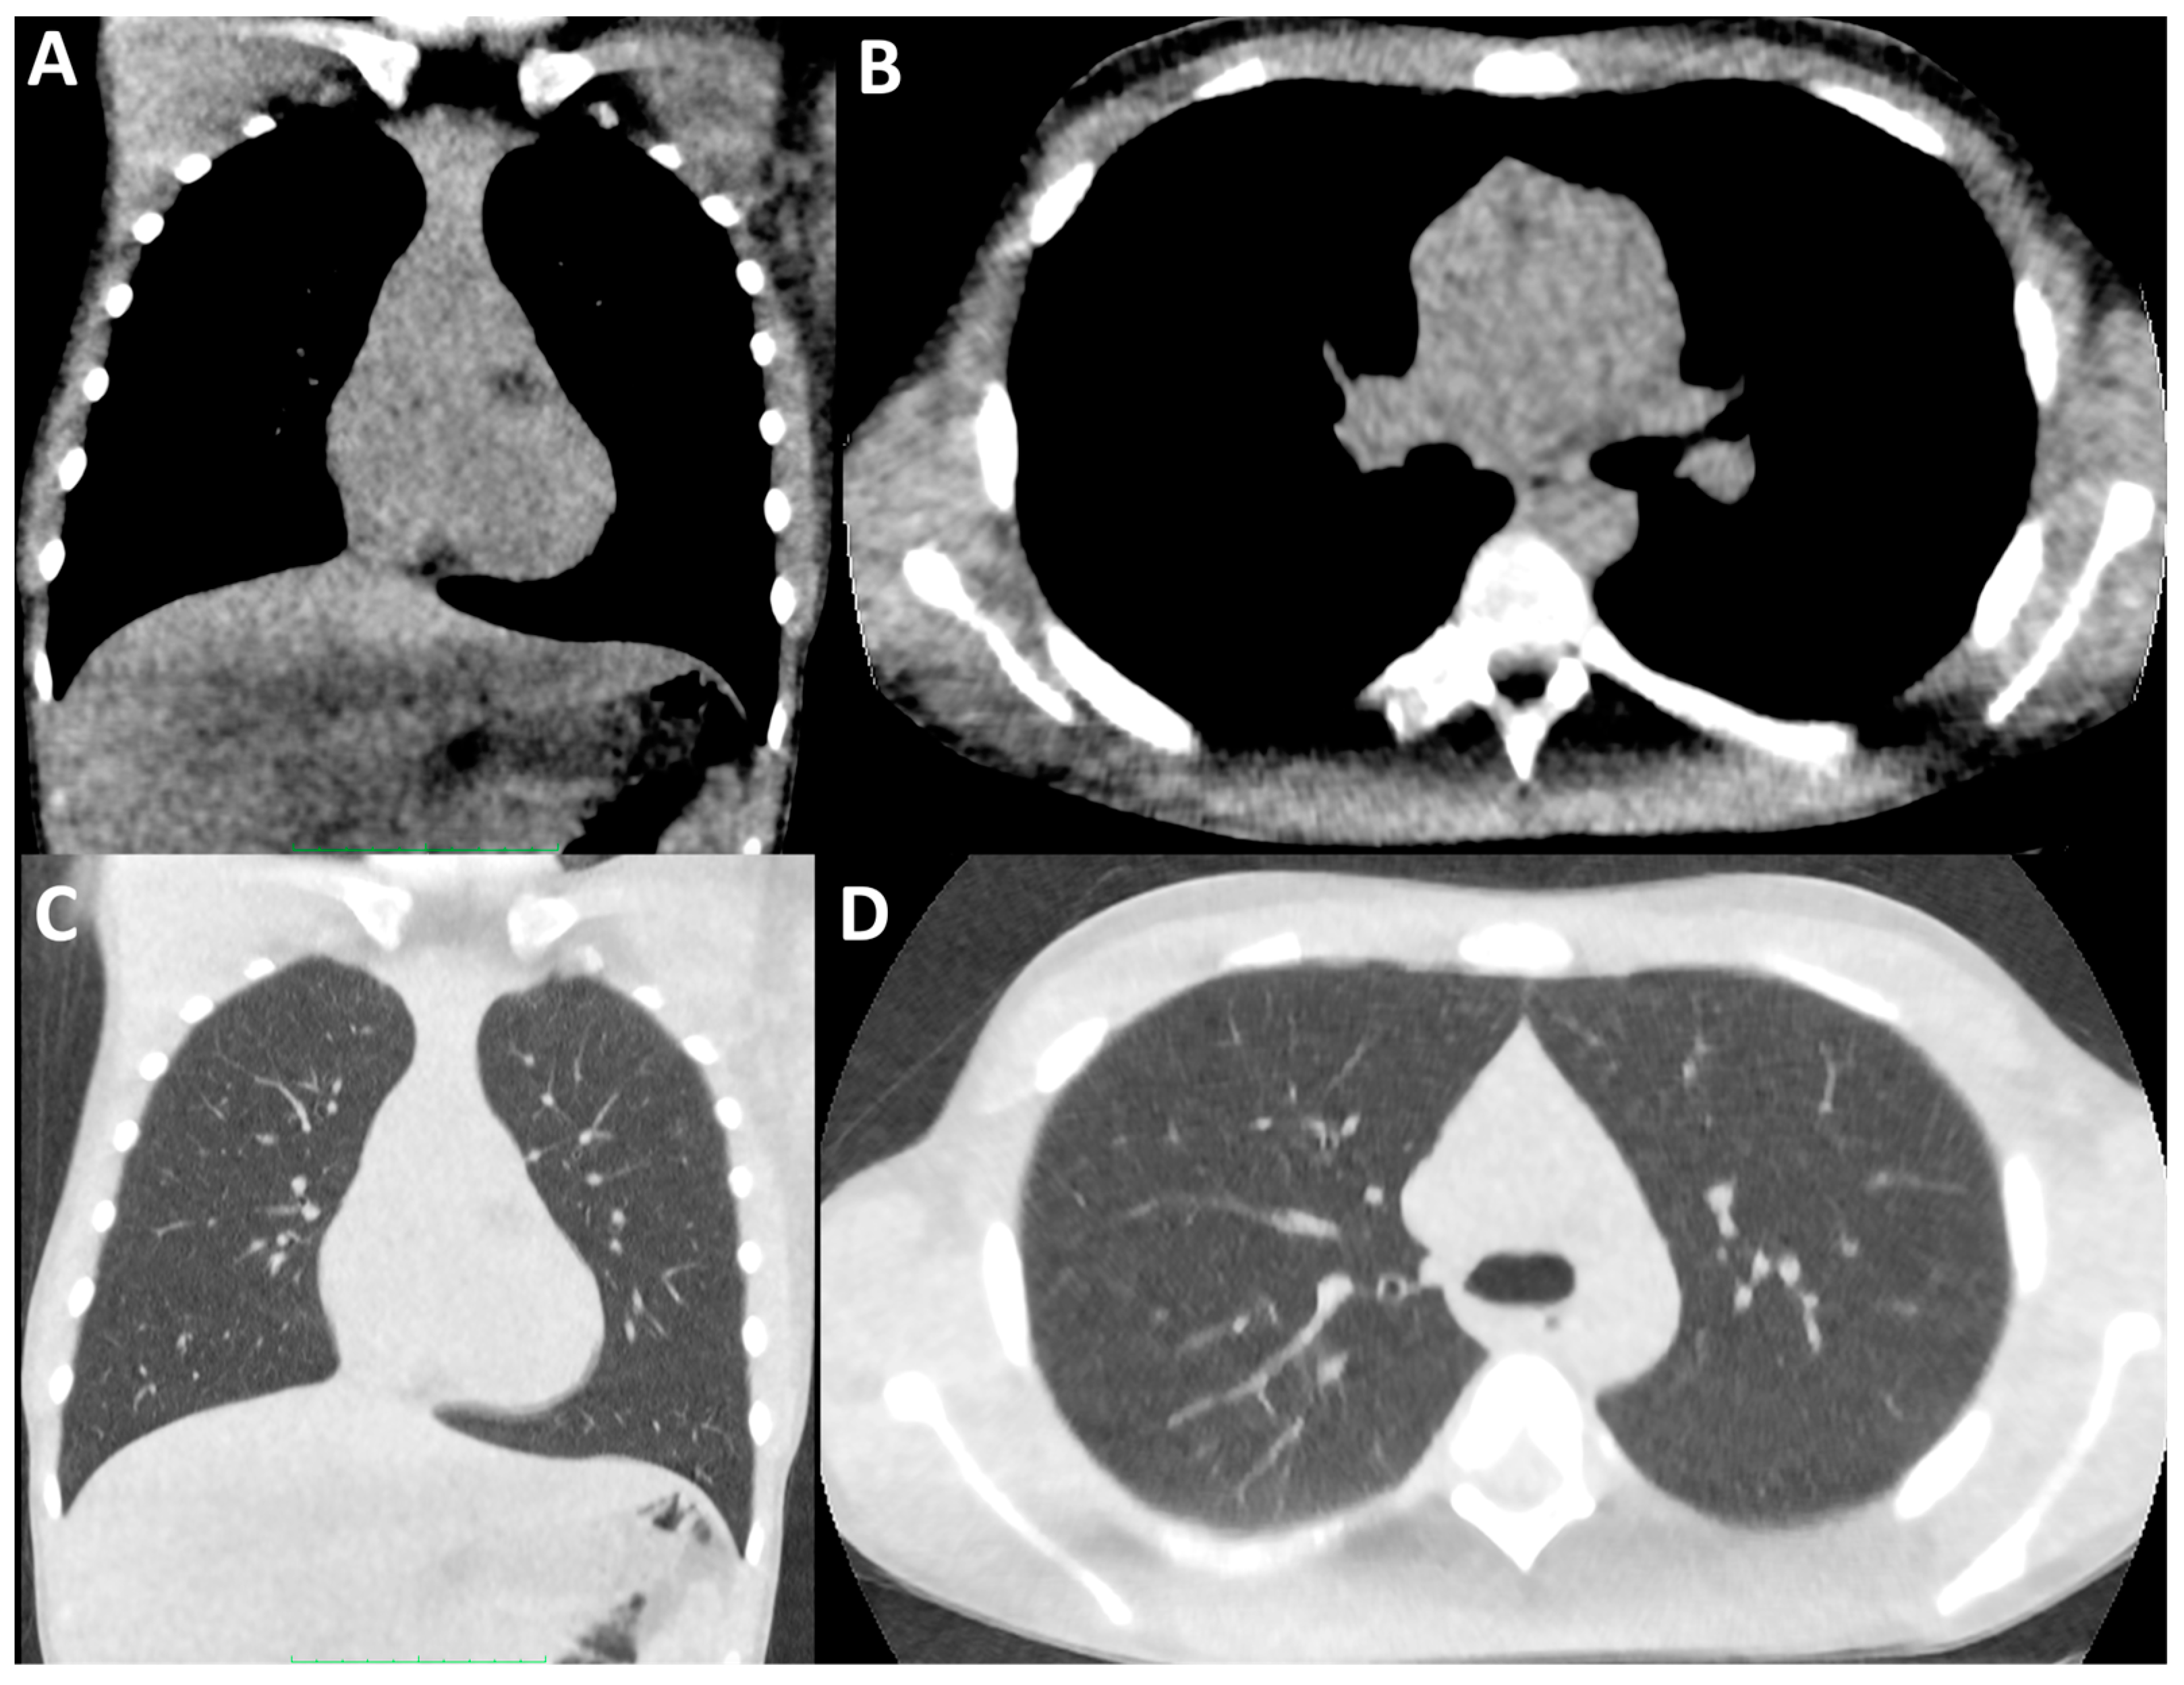

Despite these valid ionising radiation concerns, there is no internationally agreed ULDCT or LDCT thorax protocol for children with CF [86]. Our group has shown that the integration of ULDCT thorax protocols in favour of chest radiography can successfully be carried out without an increase in the cumulative effective dose in patients with CF undergoing CFTR modulation therapy [87]. Please see Figure 1 and Figure 2 demonstrating conventional-dose CT of the thorax and ultra-low-dose CT of the thorax, image quality and ionising radiation doses (39.77 mGy*cm vs. 2.28 mGy*cm, respectively) on the same male child with CF acquired several years apart.

Figure 2.

Ultra-low-dose CT of the thorax. Coronally (A,C) and axially (B,D) reconstructed ultra-low-dose CT thorax images in soft tissue (A,B) and lung windows (C,D) in the same paediatric male CF patient as Figure 1, performed during routine disease surveillance several years later. The DLP for this examination was 2.28 mGy*cm.